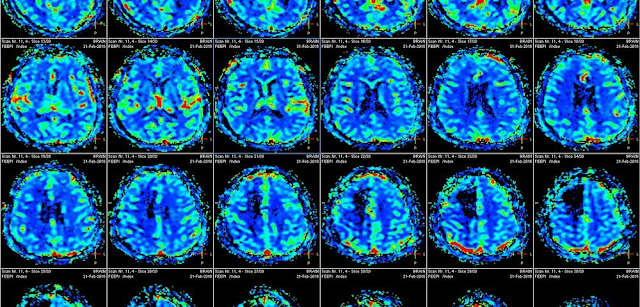

Utilizando imágenes de resonancia magnética (MRI), el equipo evaluó partes de la materia gris, y blanca, del cerebro... La materia gris está compuesta principalmente por cuerpos de células nerviosas, mientras que la sustancia blanca está formada por largos apéndices de neuronas que conectan diferentes partes del cerebro.

Tanto los pacientes con ataxia precoz, como tardía, tenían áreas en su materia gris con un volumen anormalmente pequeño. La corteza motora del cerebro estaba entre las áreas aparentemente más afectadas por la enfermedad. Este área cerebral superficial se ocupa principalmente del movimiento, y mostró un espesor reducido en ambos grupos de pacientes, en comparación con los controles sanos.

Ambos grupos también tenían estructuras anormales en varias regiones de materia blanca... Los investigadores observaron diferencias sutiles entre los pacientes que enfermaron en una edad más avanzada, y los de inicio temprano, en varias regiones del cerebro.